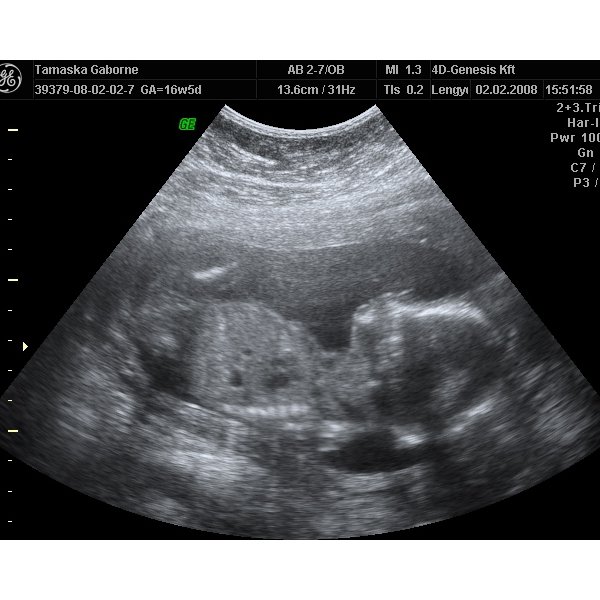

Mi még nem tudjuk, majd egy-két hét múlva belopódzom Anyuhoz egy potyaultrahangra, és megpróbáljuk kideríteni, mert a 30. heti uh-ig nem bírom ki

Jó az eü kapcsolat, mert ha akarok minden héten mehetek uh-ra.